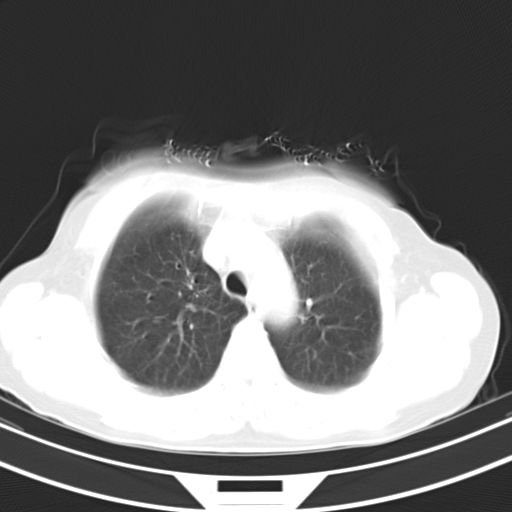

女,47岁,咳嗽胸痛一个星期,我们考虑肺结核,左下肺病灶肿瘤像不像,请高手指点。急。

右肺考虑炎症,建议抗炎后复查,左肺下叶考虑肺不张。

炎性灶;【1楔状实变影,有支气管气象,2近端纹理影增重】

右肺上叶前段积左肺舌叶炎症,建议严格抗炎后2周复查!

右肺上叶尖后段班片影不能出外肺结核。左肺舌叶三角形实变影,增强明显。考虑炎性病变